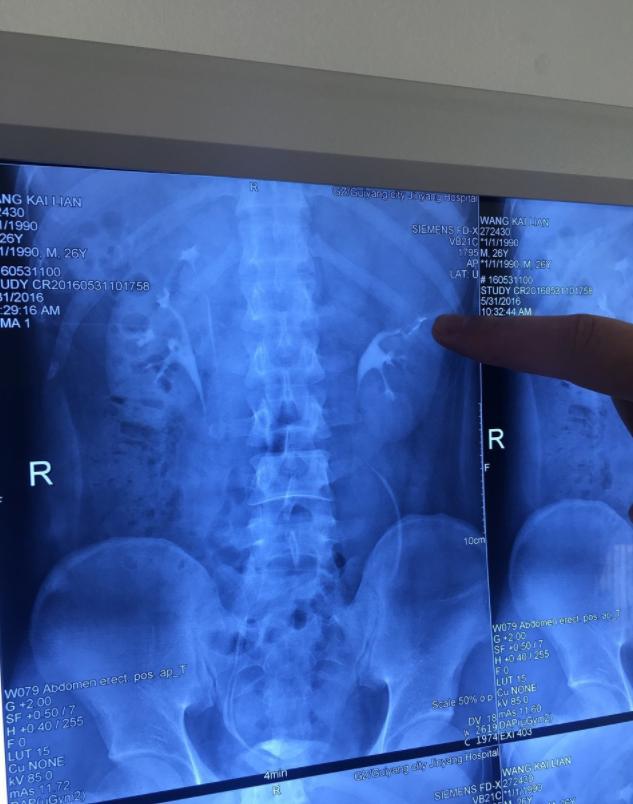

这下王开炼也熬不住了,在妻子的陪同下来到了花梨镇医院。急诊医生看过他的情况后,认为不是小事,最好先拍个片子,确定腰疼的病因究竟是什么。

很快,检查结果就出来了。然而医生看完片子后,直接愣在当场,语气凝重地说道:“小伙子,镇医院看不了,你赶紧转院吧!”

“哎呀,你这种情况我没见过,可也不是什么绝症,你得的是一种名为‘重复肾’的罕见疾病,通俗来讲,你有四个肾!”医生耐心地解释说。

2016年5月24日,王开炼来到在贵阳颇有声望的金阳医院,第三次接受诊断。

诊断结果出来后,在场的医生在震惊的同时,也对王开炼的情况羡慕不已。原因无他,因为他的的确确长了四个肾!

通常来讲,每个人都有两个肾,分别位于腹内的左右侧。而王开炼与众不同,他的左右两侧分别有两个肾,加一起一共有四个!这也能很好解释,为什么王开炼天生神力,举300斤的重物不在话下,同时还能“千杯不醉”了。

经过详细的检查后,梅医生认为,之所以王开炼体内的四个肾不显得“拥挤”,是因为他的肾比正常人小得多,每个只有婴儿拳头般大小。

同时,王开炼腰疼的原因也找到了,他的左上肾患有严重的肾积水,导致这一个肾的体积比另三个肾还大,这才出现了频繁腰疼的症状。